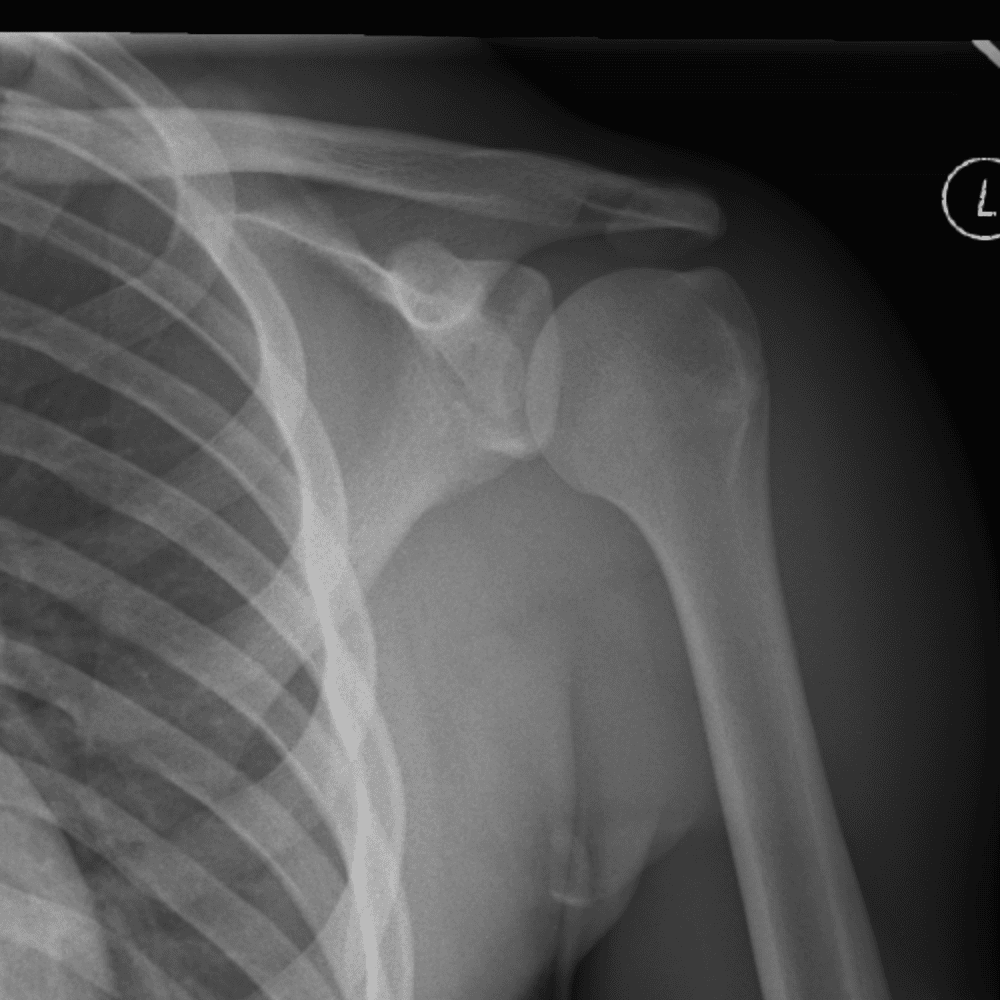

Simuliert den Dienst durch subtile oder schwierige Fälle und einige Normalbefunde.

30 Fälle